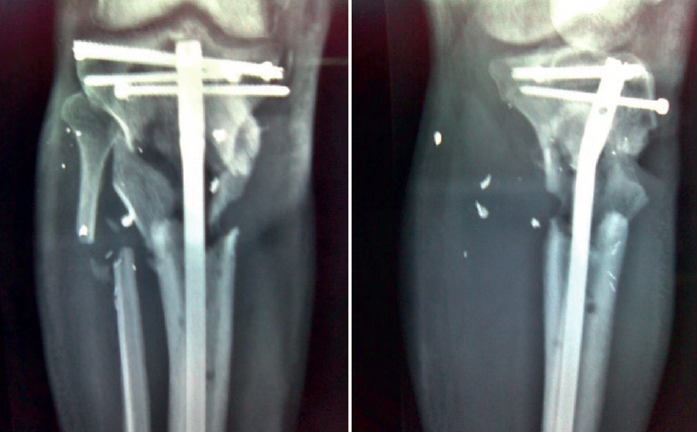

Una vez en nuestro centro, se procede a la revisión quirúrgica de la fractura, realizándose:

1. Sustitución de fijador transarticular por uno en disposición en “T” tibial, con los pines proximales uno en cada hemimeseta tibial.

2. Cierre de la fractura de meseta tibial con 2 tornillos percutáneos.

retla.05210.fs2209019-figura5.png

Figura 5. Cierre de la fractura tibial con dos tornillos canulados y colocación de pines proximales fijadores en cada hemimeseta.

retla.05210.fs2209019-figura6.png

Figura 6. Imagen radiológica intraoperatoria del cierre de la fractura de meseta y fijador externo en “T”.